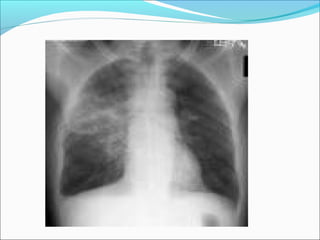

RADIOLOGIS

Setiap lobus bisa terkena sebagian atau seluruhnya

Yang sering lobus bawah

Perselubungan yang relatif homogen pada daerah

Pneumonia

Lobaris

Lobularis

(Bronkopneumonia)

Segmentalis

PA PALat Lat

Yang terkena :

LOBUS MEDIUS

LOBUS BAWAH